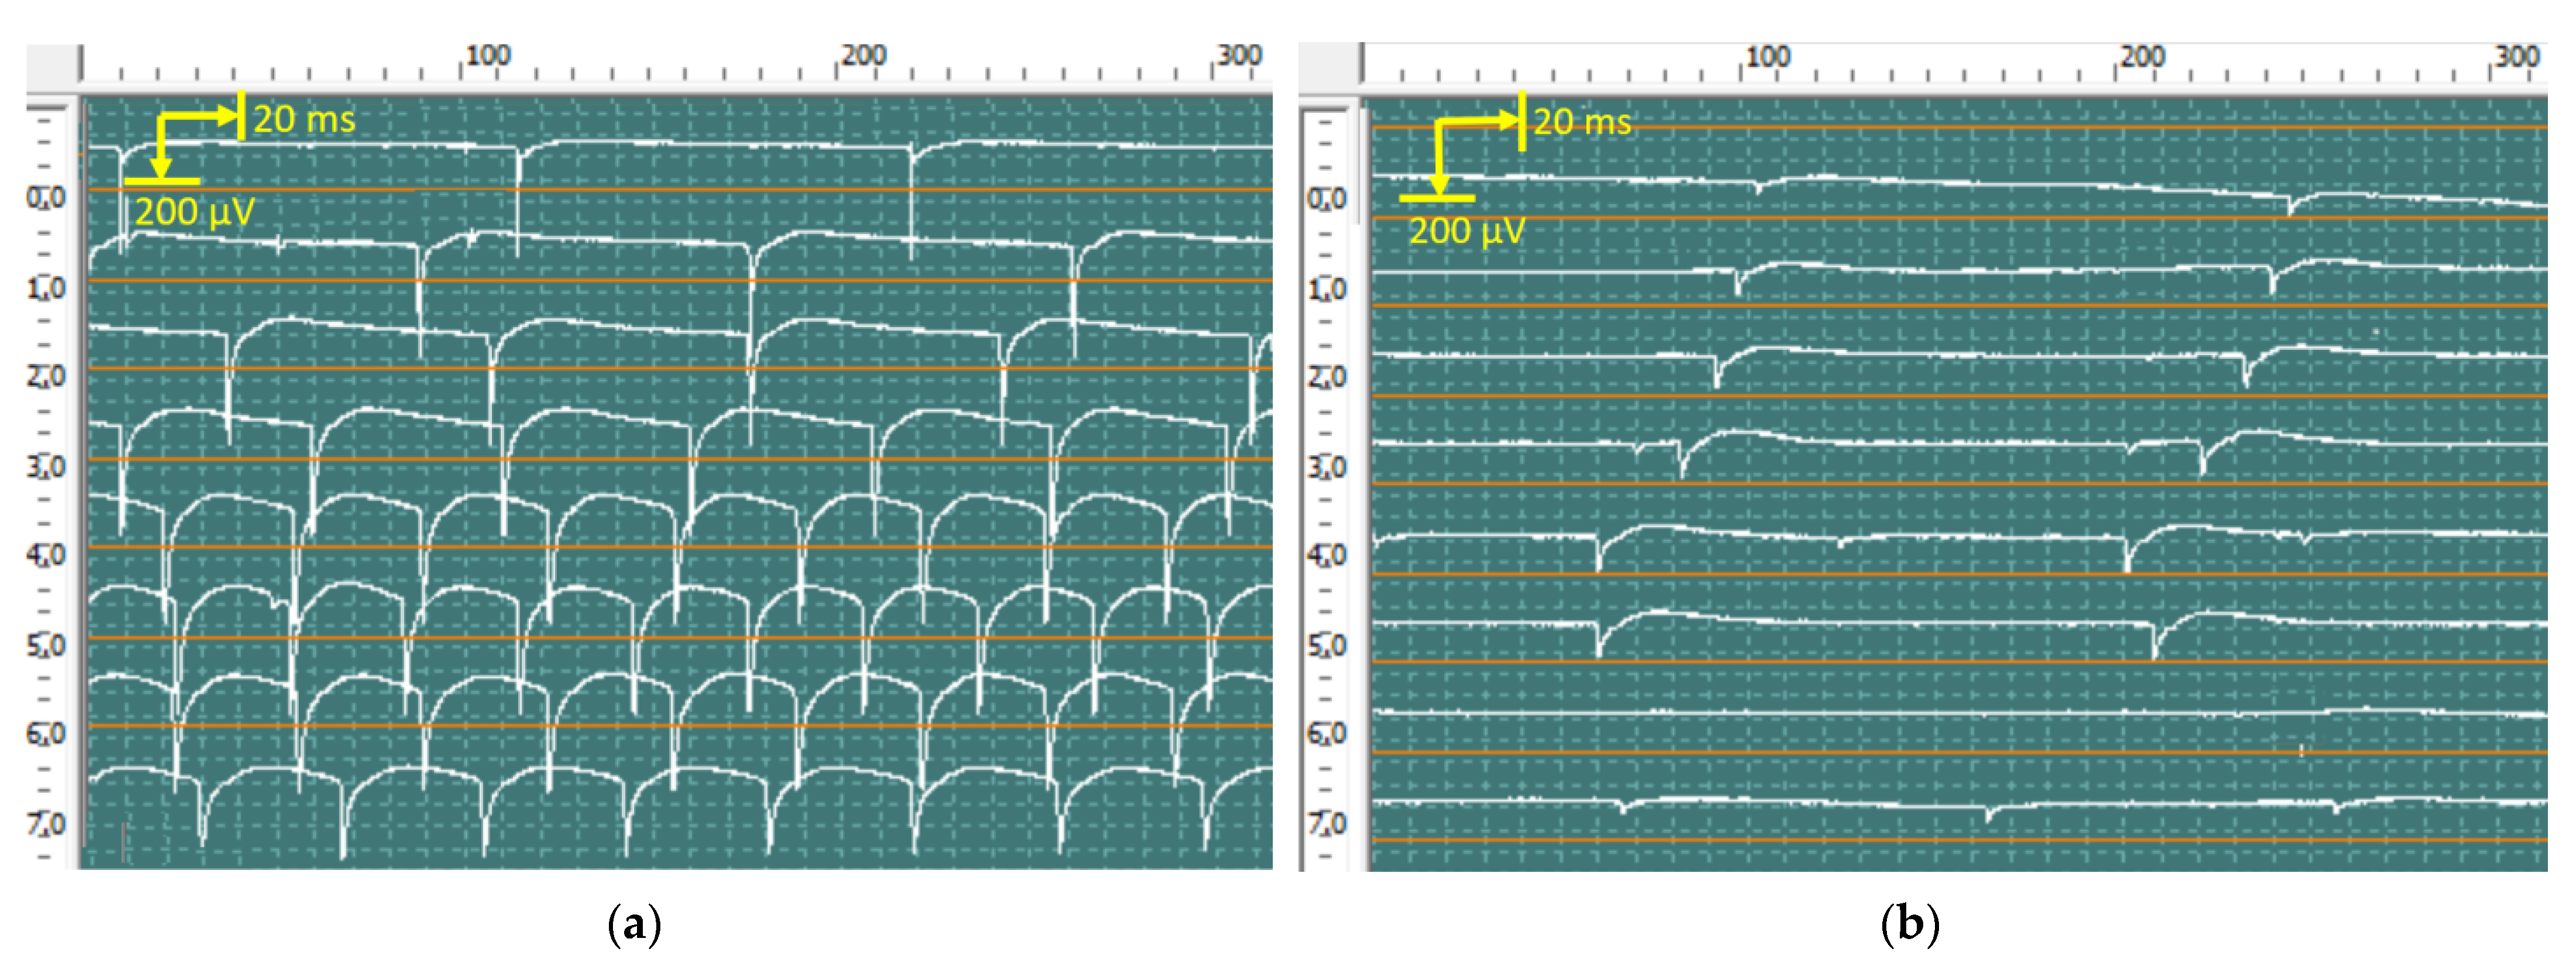

2.5.1. Evoked Electromyography

2.5.2. Quantitative Needle Electromyography